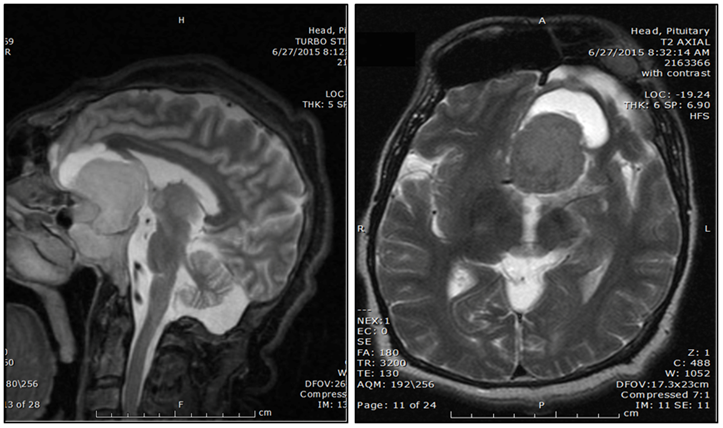

MRI of the brain (Figure 3) showed a 4.3 x 3.8 cm pituitary macroadenoma with extensive suprasellar extension and optic chiasm compression. He was evaluated by neurosurgery, but the patient refused any surgical intervention.

Figure 3 MRI of the brain showing pituitary macroadenoma. T1 Post Contrast MRI (Left) and T2 MRI of the brain (right).